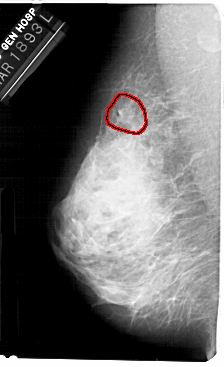

FILE: A_1361_1.LEFT_CC.OVERLAY

TOTAL_ABNORMALITIES 1

ABNORMALITY 1

LESION_TYPE MASS SHAPE IRREGULAR MARGINS OBSCURED

ASSESSMENT 3

SUBTLETY 1

PATHOLOGY BENIGN

TOTAL_OUTLINES 1

BOUNDARY